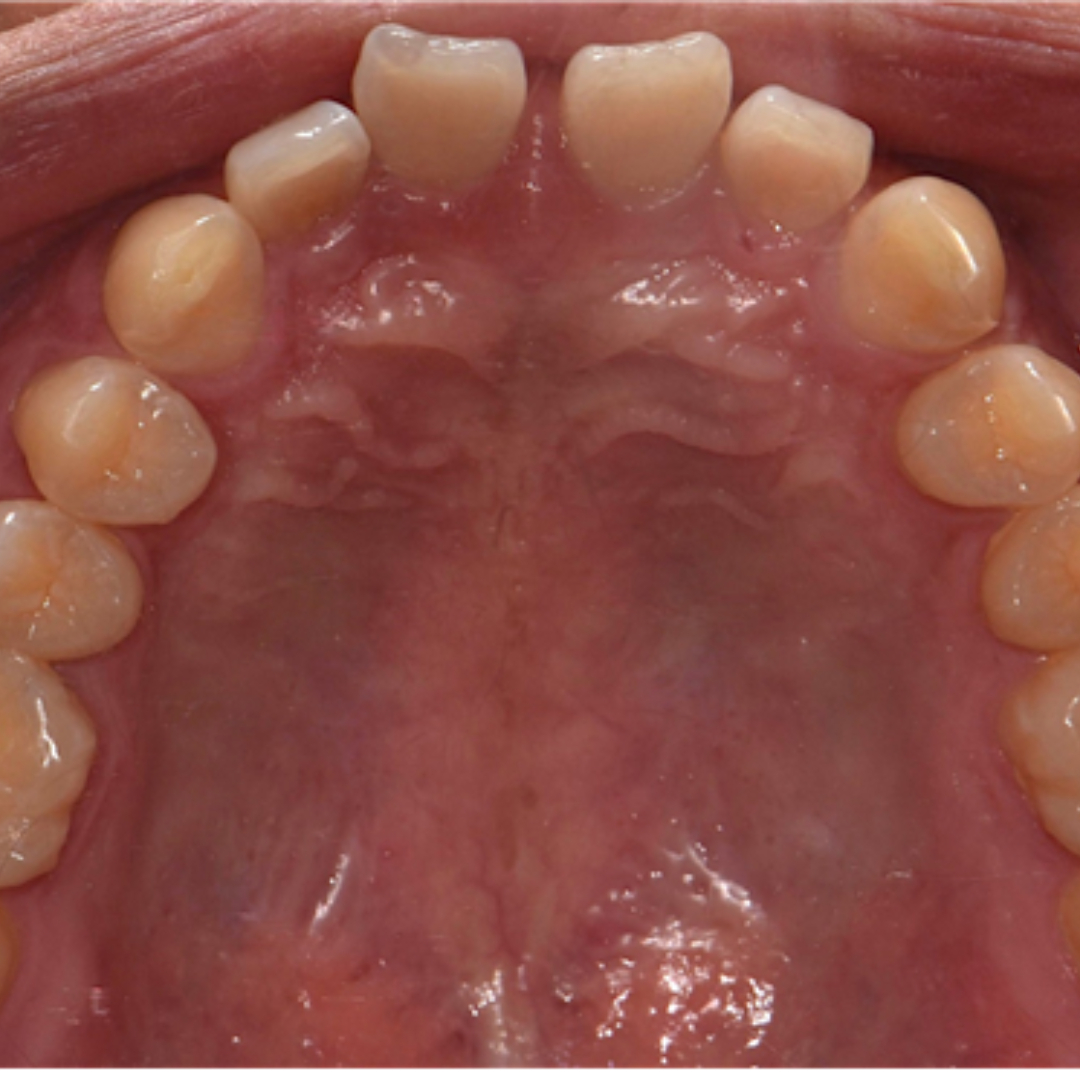

앞니 사이 벌어진 공간과 정중선 불일치를 고민으로 내원하셨던 20대 남성 환자분입니다. 윗니, 아랫니 공간이 각각 3.4mm, 2.6mm 가량 벌어져있고, 위와 아래의 중앙선 차이가 2.1mm 정도로, 상대적으로 정중이개와 정중선 불일치가 눈에 띄는 모습입니다. 해당 환자분께서는 격투기를 취미로 하시는 분이셔서 교정장치를 부착한 채로 얼굴 부위에 타격이 있을 경우 입 안이 다칠까봐 걱정이 있으셨습니다. 교정 진단 상담 후 고민 끝에 부상 방지를 위해 표면이 매끈한 투명교정 장치로 치료하시기로 결정하셨습니다.

최근에는 티 나지 않는 교정을 원하시는 심미적인 이유 뿐만 아니라, 위생 관리, 음식물 섭취, 부상 방지 등 다양한 이유로 전통적인 부착식 교정장치 대신 투명 교정을 선택하시는 환자분들이 부쩍 많아지셨습니다. 투명 교정 치료는 결과는 동일하면서 사진 촬영, 운동, 여행 등 일상 생활에 제약이 크게 없다는 점이 큰 장점입니다. 다만, 증례에 따라 부착식 교정장치가 더 빠르고 효과적인 경우도 있어 교정 치료 전 전문의와의 상담을 통해 결정하는 것이 좋습니다. ^^ 총 32주 간의 교정 치료가 종료된 모습입니다. 기존에 가장 고민이셨던 공간 벌어짐, 정중선 불일치가 예쁘게 수정되었습니다. 2025.5.18.